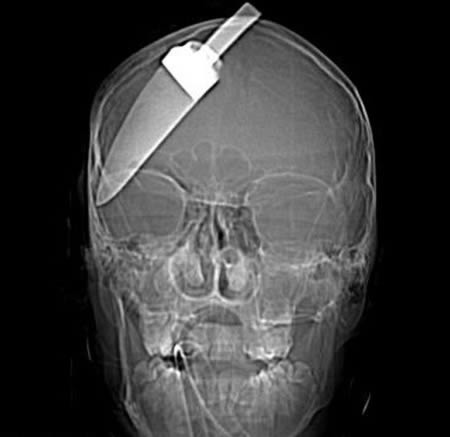

Этот 15-летний мальчик получил удар ножом в голову в тот момент, когда пытался остановить грабителей на одной из остановок Лондона. Кухонный нож вошел в голову на 18 см, и лишь благодаря мастерству хирургов мальчик остался жив.